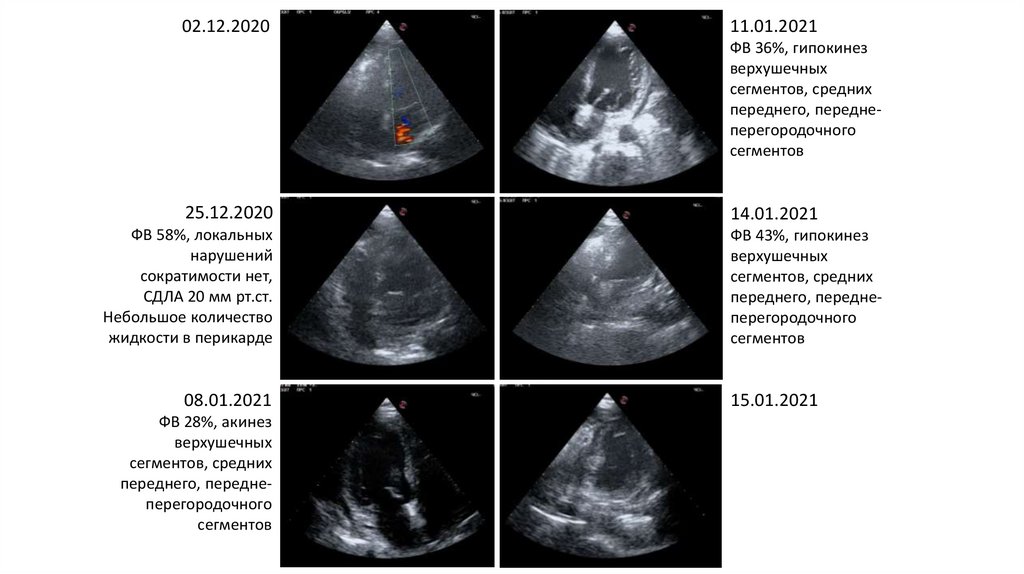

02.12.2020

11.01.2021

ФВ 36%, гипокинез

верхушечных

сегментов, средних

переднего, переднеперегородочного

сегментов

25.12.2020

ФВ 58%, локальных

нарушений

сократимости нет,

СДЛА 20 мм рт.ст.

Небольшое количество

жидкости в перикарде

08.01.2021

ФВ 28%, акинез

14.01.2021

ФВ 43%, гипокинез

15.01.2021